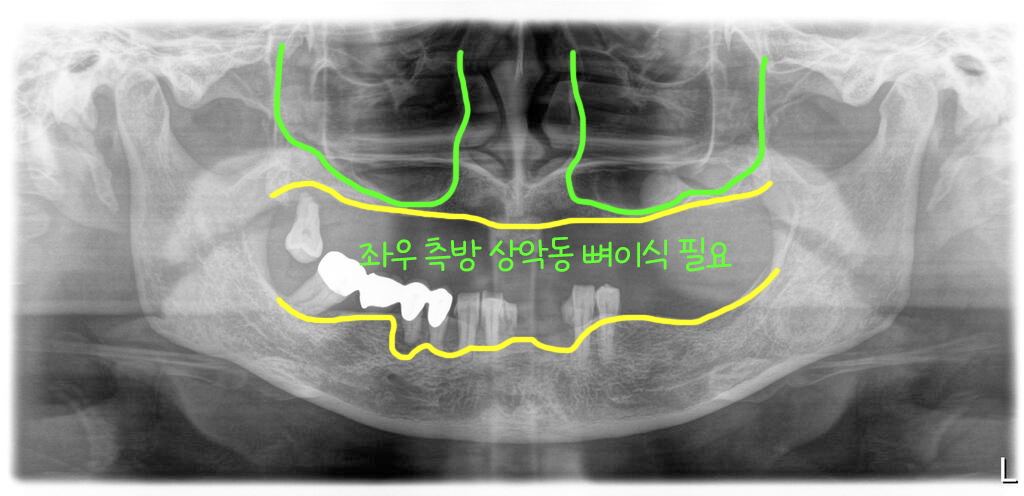

위턱에는 제일 뒤에 어금니 한 개만 남아있는 무치악 상태였습니다. 엑스레이에서 보시듯이 상악동이 앞뒤로 아주 길면서 크고 가용골(이용할 수 있는 뼈)이 전혀 없어서 뼈이식과 함께 임플란트를 식립해서 고정을 얻기가 어려운 상태였습니다.